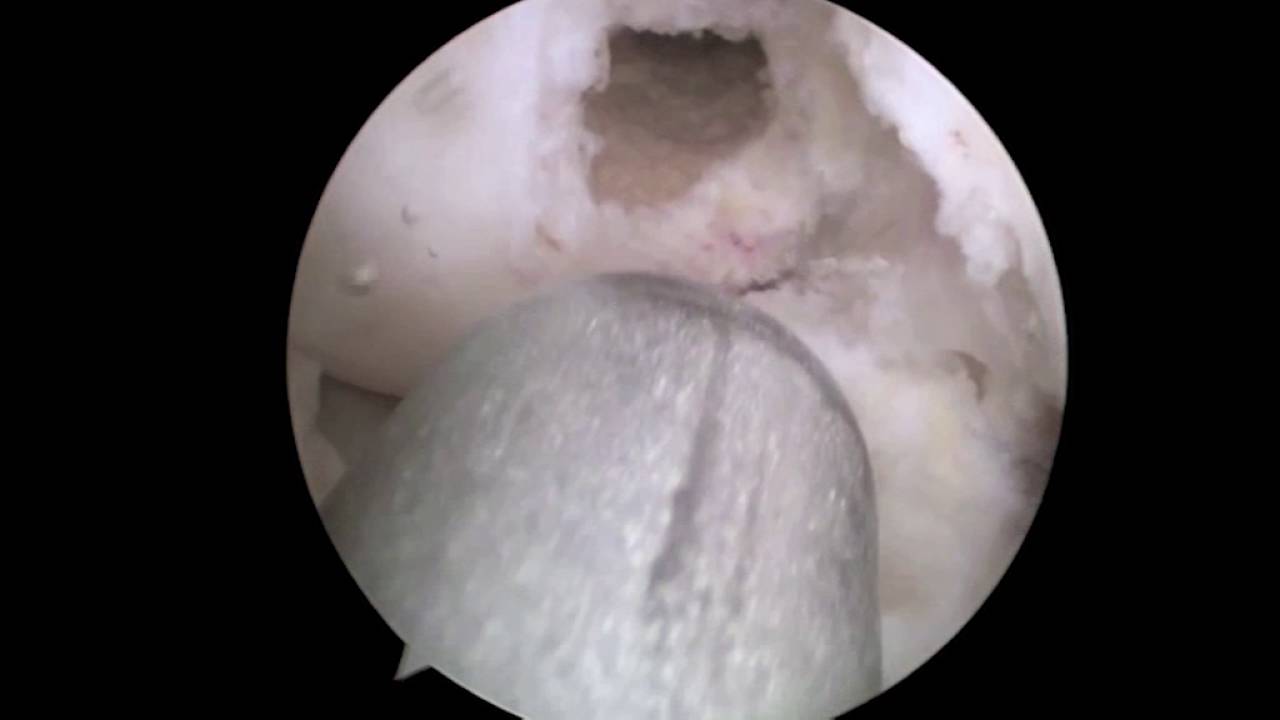

- Artroscopia

- Cirugía de menisco

- Cirugía de ligamentos

- Artrosis

- Meniscopatía

- Rotura del ligamento cruzado anterior

- Lesiones deportivas

- Condromalacia rotuliana